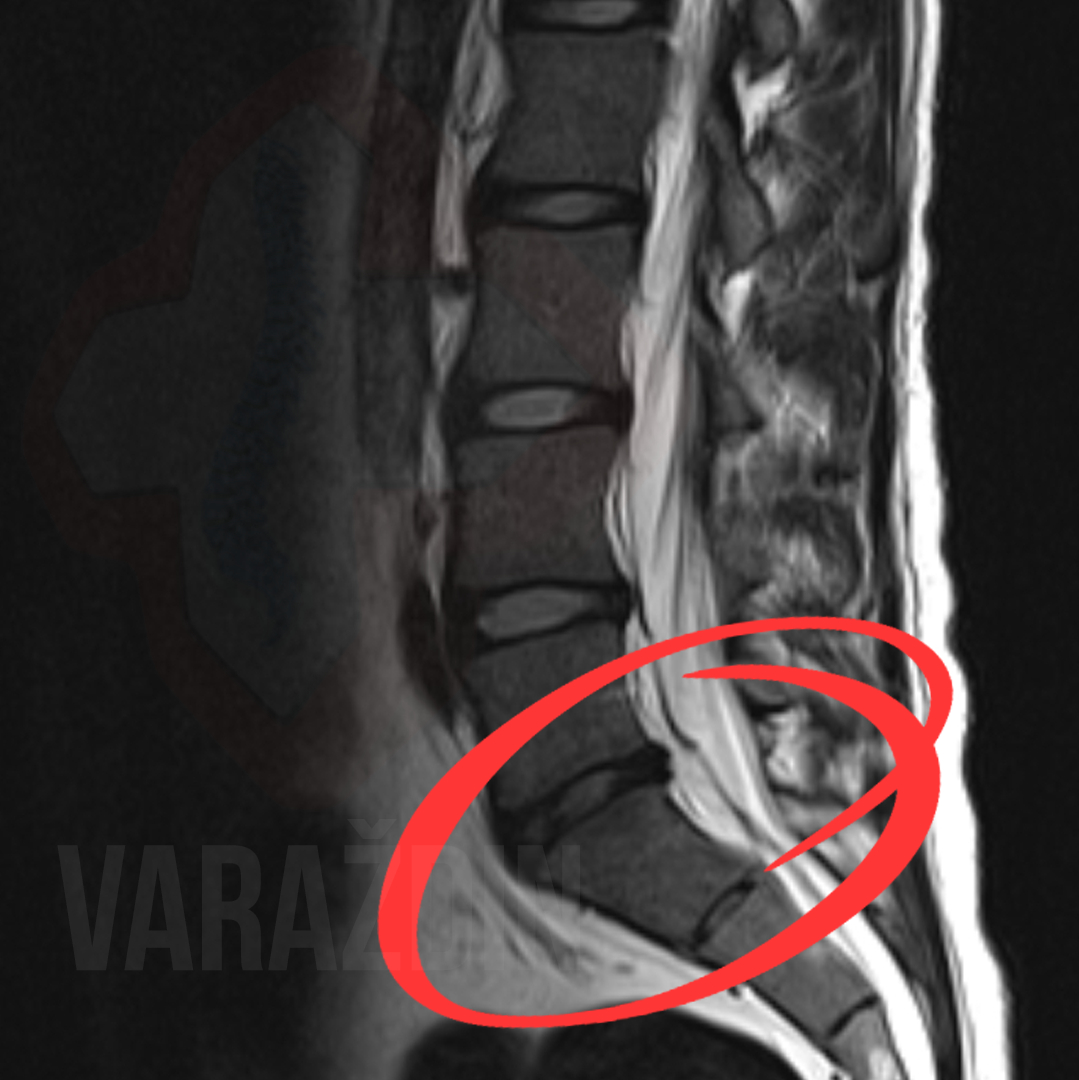

Primjer 6

Gospođa Višnja Božić javila nam se zbog izuzetno

jakih bolova koji su sezali iz lumbalnog područja kralježnice duž

desne noge, uz također u nozi prisutne trnce.

Zajedničkom odlukom krenuli smo na tretiranje lumbalne

kralježnice putem dekompresijskih tretmana. U nadi smanjenja

simptoma odluka je pala na 15-tak tretmana zbog izrazitog

ispupčenja diska na desnu stranu.

Strpljenje gospođe Božić urodilo je plodom: maksimalnom sanacijom

njenog problema. Bol i trnci u desnoj nozi potpuno su nestali.

Zahvaljujemo se na ukazanom povjerenju gospođi Višnji, a

rezultate i efekt tretmana vidjeti možete na slikama MR uz

objavu.